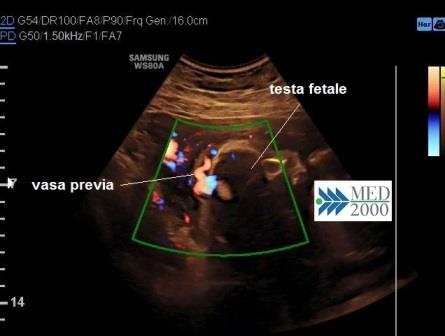

Una condizione particolare, correlata alla placenta previa, sono i Vasa previa caratterizzati da vasi fetali che decorrono lungo le membrane al di sopra della cervice e al di sotto della parte presentata. La presenza di vasa previa deve essere sospettata in presenza di una inserzione velamentosa del funicolo o in presenza di vasi anomali che decorrono tra i lobi di una placenta succenturiata. In presenza di fattori di rischio è fondamentale per la diagnosi una ecografia transvaginale con color doppler con la quale è possibile evidenziare i vasi anomali che decorrono tra parte presentata e cervice uterina. E' da precisare che nella maggior parte dei casi i vasi previ vengono identificati solo in travaglio a causa di un sanguinamento anomalo.